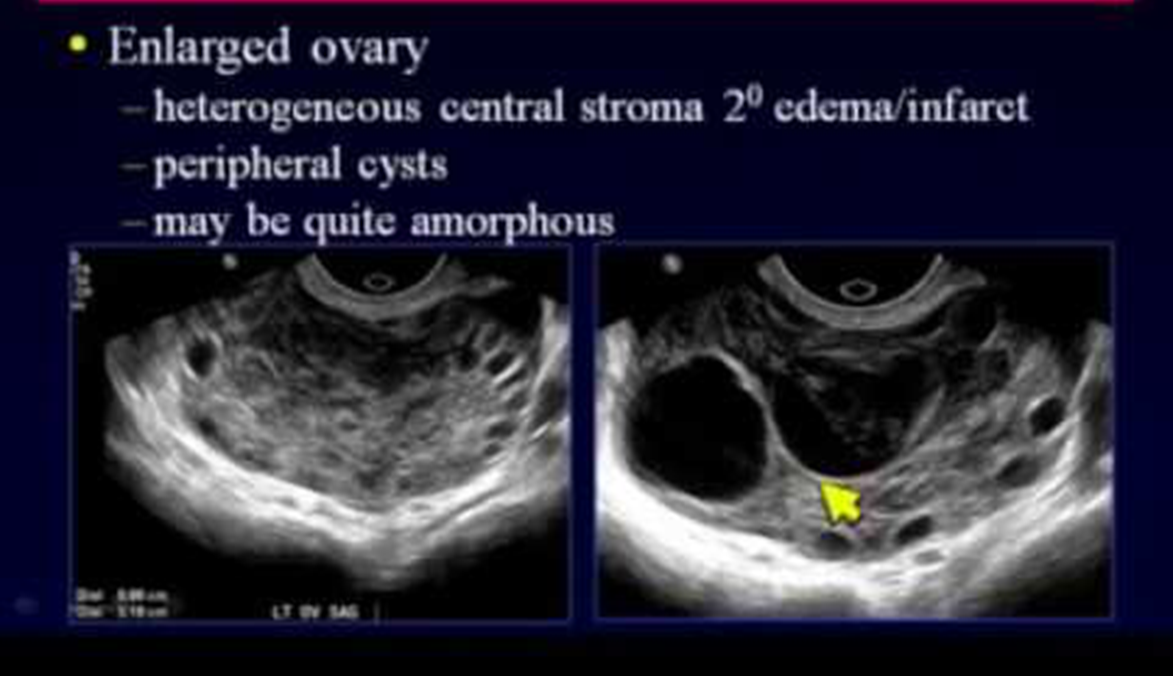

Ultrasound Pelvis is shown in the image below:

What is your most likely diagnosis?

Ovarian Torsion